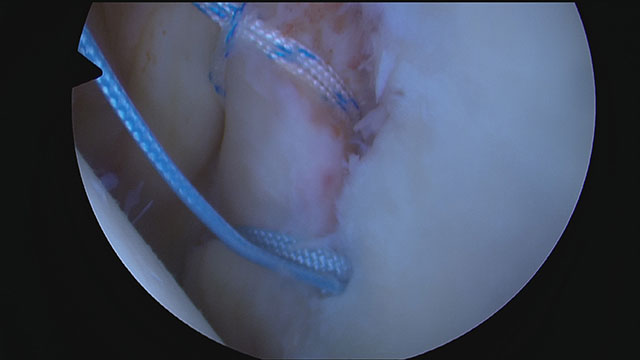

Nachdem Bohrlöcher in den vorderen Pfannenrand angelegt wurden, wird das Labrum mit Fäden angeschlungen und die Fäden mit speziellen Nahtankern in den zuvor angelegten Bohrlöchern fixiert.

Zunächst wird das Labrum umfassend mobilisiert und das Gewebe sowie der Knochen an der Pfanne angefrischt, so dass eine gute Einheilung gewährleistet ist.